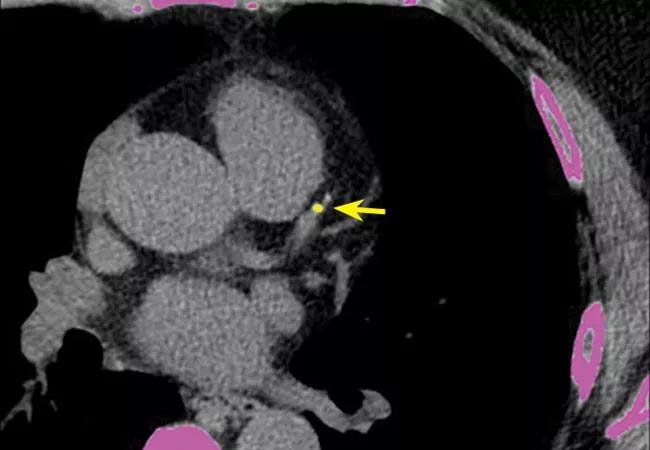

Image at top reprinted from Cleveland Clinic Journal of Medicine (2018;85:707-716).